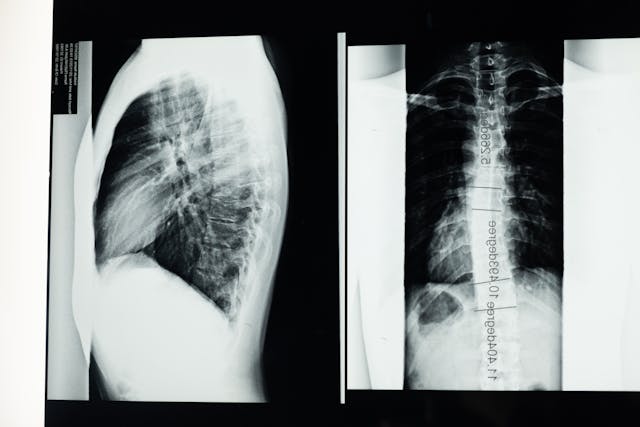

Čas od času asi každý zažije, jaké to je, když bolí záda. Někdo trpí na chronické bolesti zad, které mají většinou původ v úraze nebo nemoci. Velmi častým problémem je například skolióza nebo poúrazové stavy. Chronické boleti zad jsou velkým zásahem do kvality života, proto je žádoucí se jich začít aktivně zbavovat co nejdříve. Málokdo by ale řekl, že zbavit se bolestí zad je možné i cvičením. Své o tom ví mnozí pacienti, kteří mají skoliózu. Toto onemocnění je velmi závažné, protože výrazně snižuje kvalitu života. Při výraznějším zakřivení páteře je dokonce nutné řešit ji operativně.

Pokud vás trápí skolióza, jistě vás lékař odeslal s doporučením k fyzioterapeutovi, který vám nastínil, jaké máte možnosti. Se skoliózou se skutečně musí zajít k fyzioterapeutovi, který váš stav na základě podkladů z vyšetření od lékaře zhodnotí a určí, jaký pro vás bude nejlepší postup. Velmi efektivní jsou speciální cviky na skoliózu, které jsou známé pod svým názvem SM systém. SM systém je velmi účinný typ cviků. Jsou to cviky, které sestavil pan doktor Smíšek a které mají za výsledek srovnání páteře při menších stupních zakřivení. Posilují svaly celého hrudníku, díky čemuž se začne páteř pozvolna srovnávat. Aby k tomu došlo, je nutné cvičit pravidelně a hlavně správně. S tím vám pomůže právě váš fyzioterapeut.